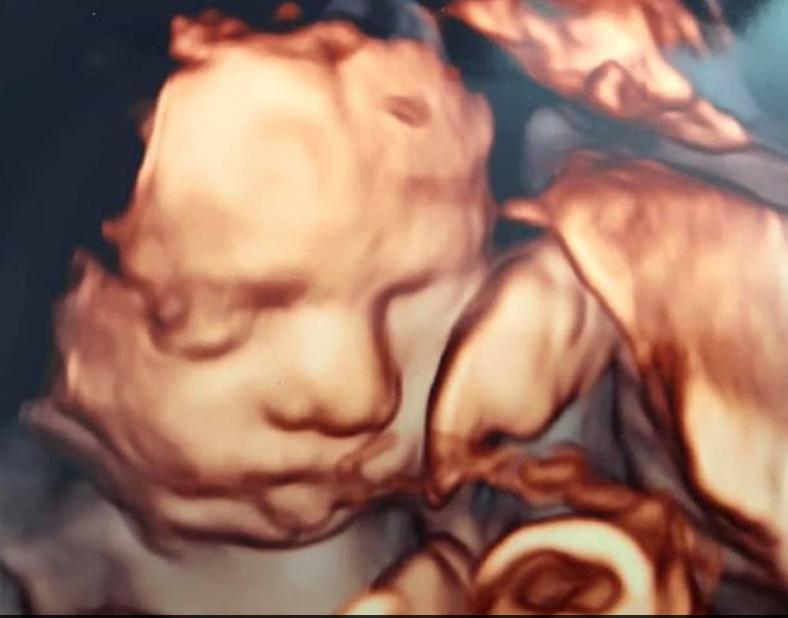

小宝宝玛雅·洪卡(Maya Honca)还未出生时,就在一次孕检中被医生发现股骨骨折,后被诊断患有成骨不全症(也称为脆骨病)。

2019年1月,37岁的艾玛·汤姆林森(Emma Tomlinson)怀孕20周时,在32岁的丈夫路易斯·洪卡(Louis Honca)的陪伴下来到医院做产检。在一次例行扫描后,这对夫妇被告知胎儿"有异常"。